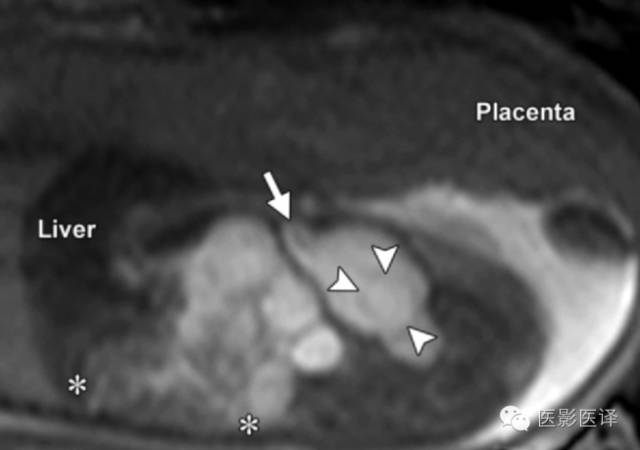

图3:单纯性卵巢囊肿。(a)矢状位胎儿超声图像显示一个边界清楚薄壁腹内囊肿(箭头),其内可见一个子囊(箭)。囊肿位于膀胱(B)上方腹中线区。Uv=脐静脉。(b)同一病人轴位超声多普勒图像显示在薄壁卵巢囊肿中有两个子囊(箭头)

胎儿卵巢囊肿5.6厘米会消失吗,卵巢巨大囊肿与妊娠鉴别